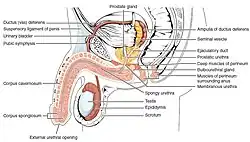

Pénis (português europeu) ou pênis (português brasileiro) humano é o órgão sexual copulatório masculino que também é o responsável pela micção.[1][2] As principais partes são: a raiz (radix); o corpo (corpus); e o epitélio do pénis incluindo o corpo cavernoso e o prepúcio cobrindo a glande.[1] O corpo do pénis é constituído de três colunas de tecidos: dois corpos cavernosos, os dorsais e o corpo esponjoso entre os anteriores no lado ventral. A uretra humana masculina passa através da glândula prostática onde une-se com o ducto ejaculatório através do pénis.[3] A uretra atravessa os corpos esponjosos, e a sua abertura, o meato, dependo do tipo de glande. É a saída excretora para a micção e ejaculação de sémen.[2] A maior parte de desenvolvimento do pénis é composto polo mesmo tecido embrionário que o do clítoris nas mulheres; a pele arredor do pénis e da uretra provém do mesmo tecido embrionário do qual são feitos os lábios menores nas mulheres.[4][5] A ereção[6] é a mudança de estado do pénis, o qual expande-se aumentado de tamanho e ficando teso e duro; isto acontece durante a excitação sexual, porém, também pode ter lugar em situação não-sexuais. A alteração genital mais comum é a circuncisão,[7] a remoção parcial ou total do prepúcio por vários motivos; culturais, religiosos e mais raramente, médicos.[7][8] Há bastante controvérsia acerca da circuncisão.[9]

O pénis humano é formado por três colunas de tecido: dois corpos cavernosos situam-se lado a lado no lado dorsal e um corpo esponjoso entre eles no lado ventral.[11]

A extremidade alargada e em forma de bulbo do corpo esponjoso forma a glande do pénis com dois tipos específicos de sinusóides, que sustentam o prepúcio, uma prega de pele solta que em adultos pode retrair para expor a glande.[12] A área no lado inferior do pénis, onde o prepúcio é ligado, é chamado o frênulo prepucial. A base arredondada da glande é chamada de coroa. As glândulas Prepuciais, situadas na coroa, secretam substâncias que compõem a secreção esbranquiçada que recobre o pênis, o esmegma.[13] A rafe perineal é a linha perceptível ao longo da parte inferior do pénis.

A uretra, é a última parte do tracto urinário, atravessa o corpo esponjoso, e a sua abertura, conhecida como o meato ureteral, situa-se sobre a ponta da glande do pénis. É uma passagem tanto para a urina quanto para a ejaculação do sêmen. Os espermatozoides são produzidos nos testículos e armazenados no epidídimo anexado. Durante a ejaculação, os espermatozoides são impulsionados pelos canais deferentes, dois ductos que passam por cima e por trás da bexiga. Os fluidos são adicionados pelas vesículas seminais e os vasos deferentes transformam-se nos ductos ejaculatórios, que se unem à uretra dentro da próstata. Tanto a próstata quanto as glândulas bulbouretrais adicionam mais secreções e o sêmen é expelido pelo pénis.

Nos homens, a expulsão da urina do corpo é feita pelo pénis. A uretra drena a bexiga através da próstata, onde é unida pelo ducto ejaculatório e, em seguida, para o pénis. Na raiz do pénis (a extremidade proximal do corpo esponjoso) está o músculo esfíncter externo . Este é um pequeno esfíncter de tecido muscular estriado e está em homens saudáveis sob controle voluntário. O relaxamento do esfíncter da uretra permite que a urina na parte superior da uretra entre no pénis de maneira adequada e, assim, esvazie a bexiga.